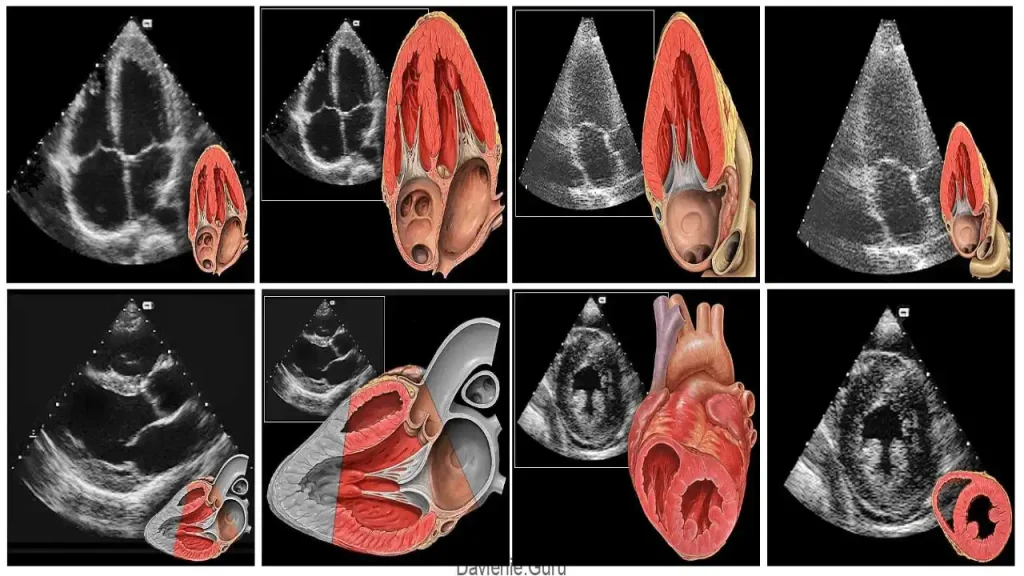

اکو قلب جنین یا Fetal Echocardiography نوعی سونوگرافی تخصصی است که به پزشکان امکان میدهد ساختار و عملکرد قلب جنین را در دوران بارداری با دقت بالا بررسی کنند. در این روش، دستگاههای پیشرفته با استفاده از امواج فراصوت تصویری دقیق از قلب، بطنها، دهلیزها، دریچهها، عروق اصلی و حتی ریتم قلب جنین ایجاد میکنند. به همین دلیل، اکو قلب جنین یکی از ابزارهای حیاتی برای تشخیص زودهنگام مشکلات قلبی محسوب میشود.

- کیفیت تجهیزات: دستگاههای پیشرفته با قابلیت Doppler و تصویربرداری سهبعدی دقت تشخیص را بسیار افزایش میدهند. به همین دلیل مراجعه به بهترین مراکز اکو قلب جنین اهمیت زیادی دارد.